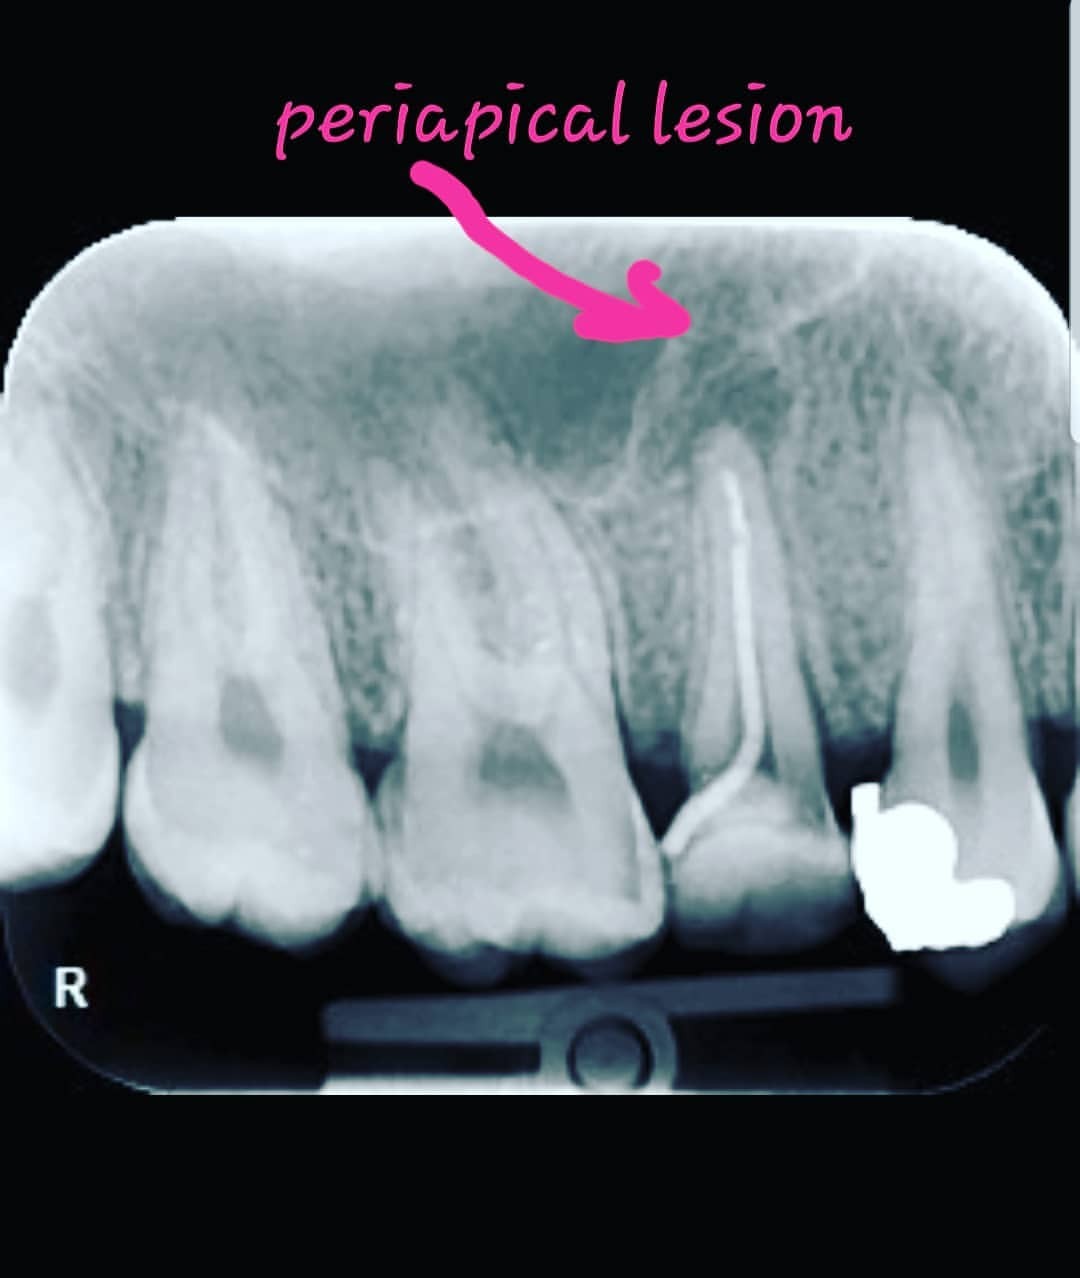

این نوع کیستها که در ناحیه فک به وجود میآیند دارای دو نوع هستند: نوع اول کیست با منشأ التهابی و نوع دوم کیست با منشأ تکاملی است. مهمترین و شایعترین کیستها، کیست رادیکولار یا پری آپیکال است. این کیست از جمله کیستهای مربوط به ریشه دندان است که بخاطر پوسیدگی دندان یا عفونت دندان ترمیم شده به وجود آمده است. به غیر از کیست پریاپیکال که شایعترین کیست التهابی است در اینجا دو نوع کیست دیگر فولیکولار و تومورهای ادونتوژنیک کراتوسیستیک را مورد بررسی قرار میدهیم.

این نوع کیست شایعترین نوع کیست دهان و دندان است که با نامهای مختلفی چون کیست پریودنتال، کیست دندان و یا کیست ریشه معروف است. علت بروز این کیست از بین رفتن پالپهای موجود دررون دندان است. پالپها بر اثر پوسیدگی و یا ضایعههای دندانی از بین میرود. درمان این کیست معمولاً با روش ENDO صورت میگیرد. در این روش متخصص با روشهای جراحی به انتهای عصب فرد دسترسی پیدا میکند تا کیست و یا عفونت را بردارد. در برخی مواقع درمان ENDO تاثیر گذار نیست و متخصص مجبور به کشیدن دندان میشود تا محل کیست را تمیز کند سپس با مواد مصنوعی آن ناحیه را پر میکند.